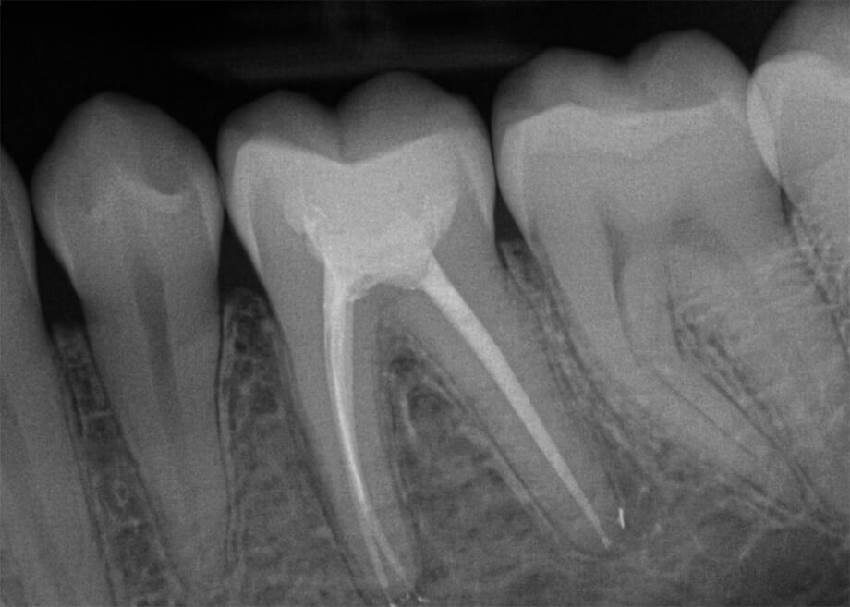

2)Прицельный снимок :

Прицельный снимок зуба - информативнее и точнее чем панорамный , но он очень мал ,в нём помещается 2-3 рядом стоящих зуба. И всё равно он двухмерный , т.е мы можем посмотреть на зуб практически только с одной стороны ,как на фотографию. При этом искажений в нем будет гораздо меньше , даже могут быть видны разные мелкие детали.

Видны некоторые кариесы, пломбы на зубе и внутри корневого канала, воспалительные проявления в кости около зуба. И мы часто его используем в практике для диагностики определенного зуба. Рентгенологическая нагрузка при этом крайне мала - менее 3 микрозиверт.